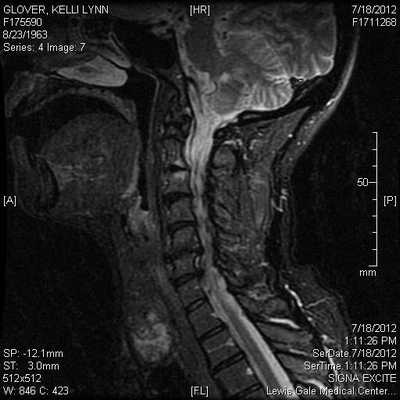

(Справа) КТ с КУ, сагиттальная проекция. Характерная картина лимфоцеле: однодольчатое образование округлой или овальной формы, лишенное перегородок, имеющее жидкостную плотность. Располагается киста в надключичной ямке, не накапливает контраст и не имеет различимых стенок.

3. МРТ при лимфоцеле шеи:

• Т1ВИ с КУ:

о При отсутствии осложнений контраст не накапливает

• Жидкостной сигнал на всех последовательностях

5. Рекомендации по визуализации:

• Лучший метод визуализации:

о КТ с КУ

о УЗИ полезна, особенно для контроля биопсии